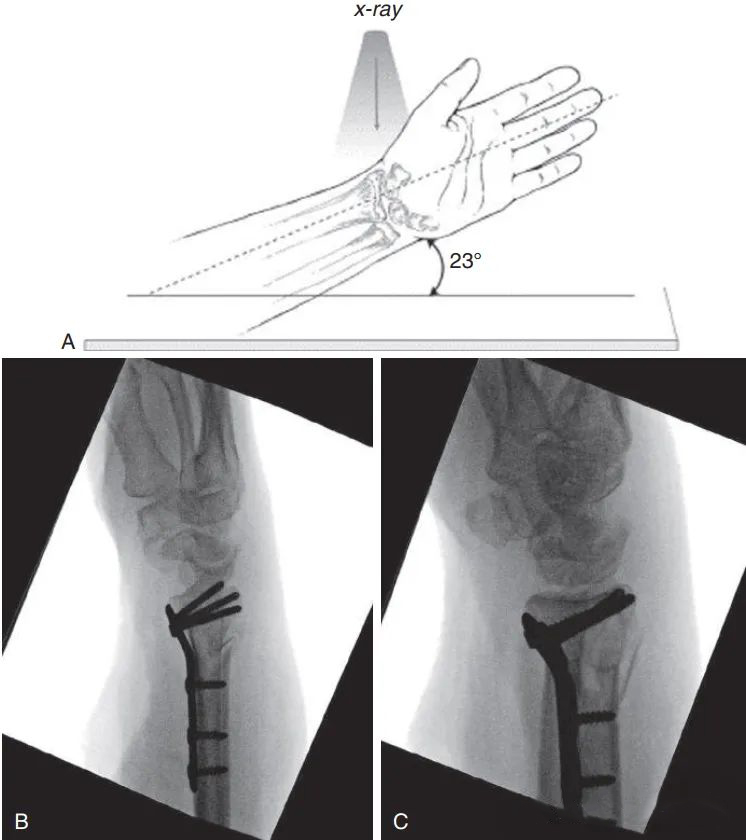

Доступ Генри — наиболее часто используемый хирургический доступ на ладонной стороне лучевой кости. Он входит между лучевой артерией и лучевым сгибателем запястья и заканчивается дистальнее поперечной складки запястья (некоторые ученые используют Z-образный разрез или расширяют его). напрямую).

Общий доступ к дистальному концу лучевой кости с прямым расширением дистального конца (Источник изображения: DOI: 10.1007/s00064-015-0433-5)

Z-образный разрез по дистальной складке запястья (Источник: DOI: 10.1007/s00064-023-00818-6).